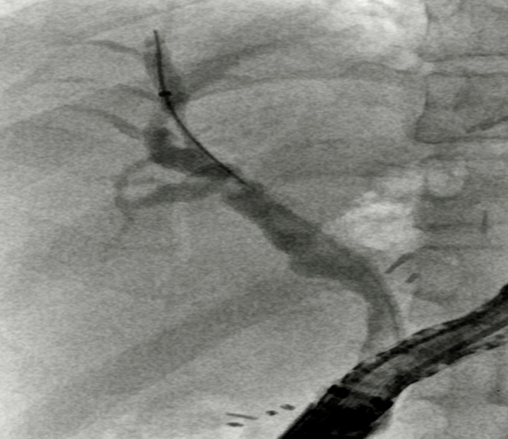

Ultrasonography showed a suspicious left hepatic duct stone with a dilated common bile duct and left biliary radicals. A contrast enhanced computed tomography scan of the abdomen and pelvis demonstrated an atrophic left lobe with multiple hypodense liver lesions suggestive of stones, particularly in segments II and III, with the largest measuring approximately 4 cm, likely representing a liver abscess with a cluster sign due to recurrent pyogenic cholangitis (Figure 1). MRCP confirmed evidence of a dilated left intrahepatic bile duct with multiple stones, associated with edema of the left liver lobe, findings consistent of oriental cholangiohepatitis. The common bile duct was dilated with multiple small stones (Figure 2). Patient underwent ERCP using Spyglass that failed to opacify the Left IHBR by to complete obstruction of the LHD due to giant stone. CBD clearance was performed with plastic stent insertion (Figure 3).

Figure 4. ERCP revealing large stone obstructing the LHD (star), Deployment of biliary stent (arrow).